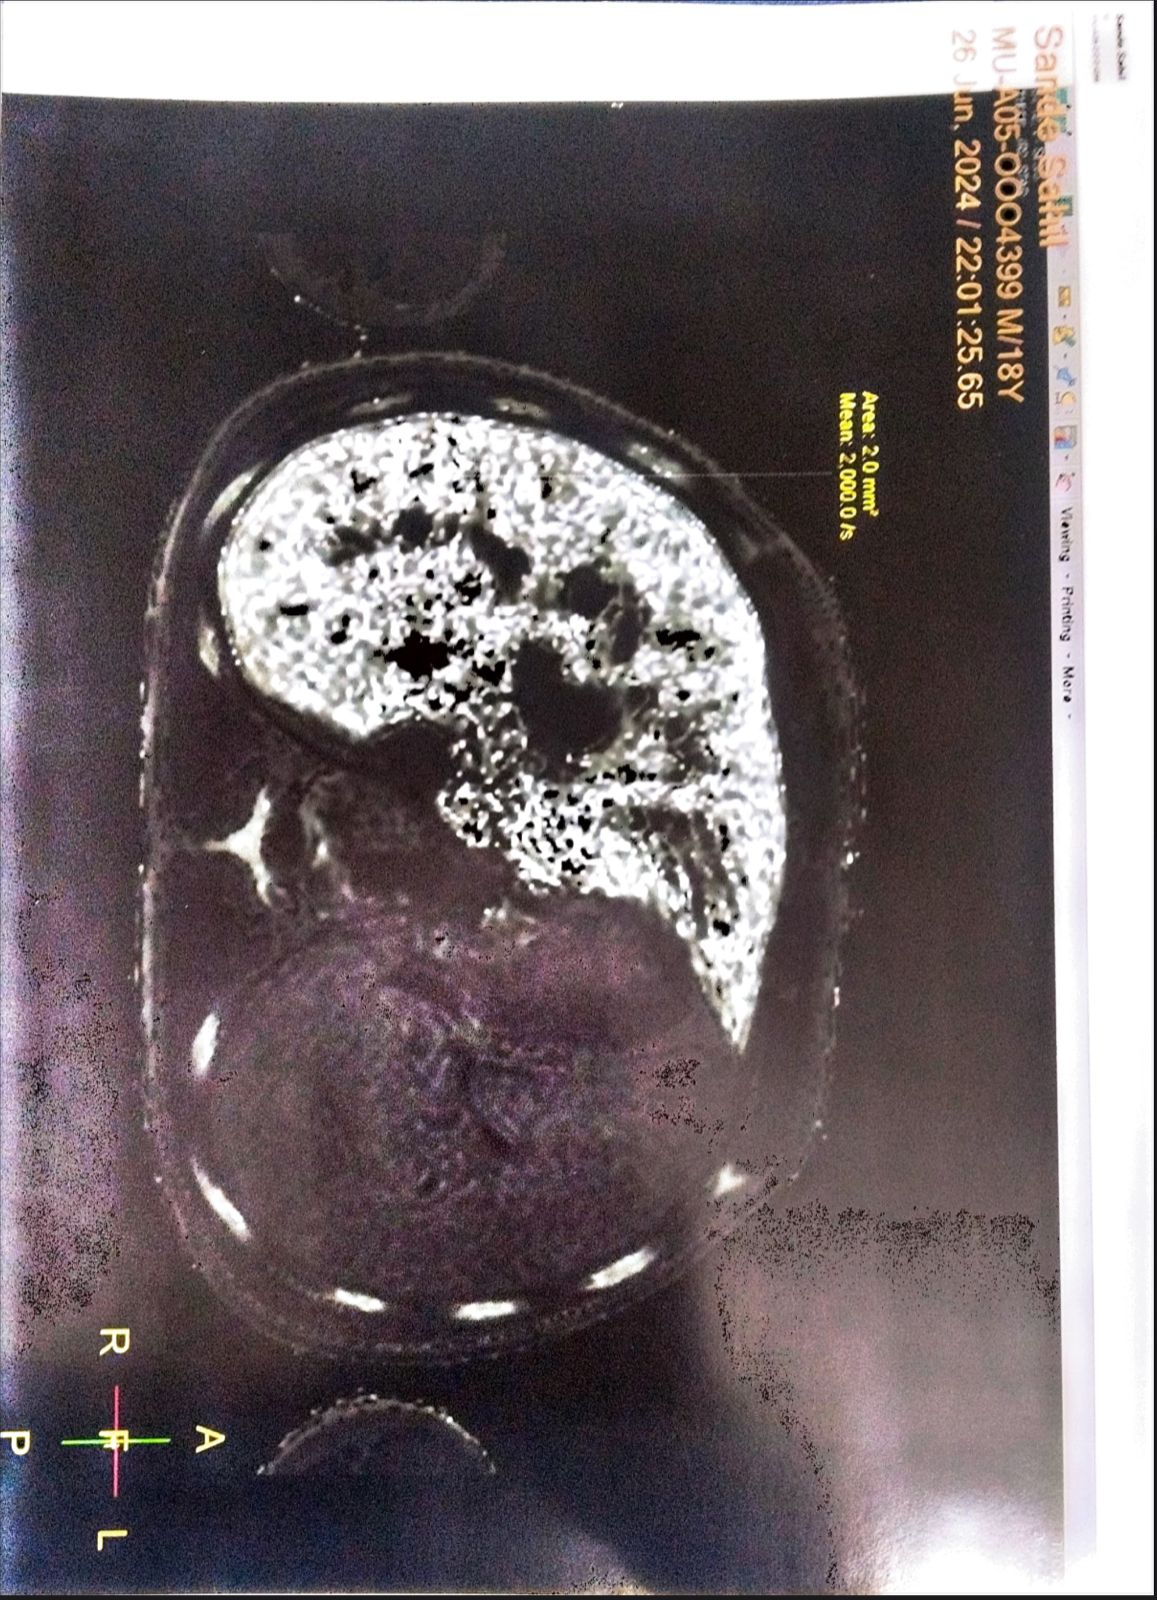

This is to certify that Mr. Sahil Sameer Sanade ,age 18 years Boy,

suffering Thalassemla Major (MUD ) matched unrelated donor

Presently receiving treatment under Ruby Hall Clinic

He is planned for Allogenic Bone Marrow Transplant.